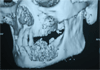

Case presentation: We described a case of metastatic follicular thyroid carcinoma to the mandible presenting with pain and loosening of teeth in a 70 years old female patient leading to extraction of the loose teeth.